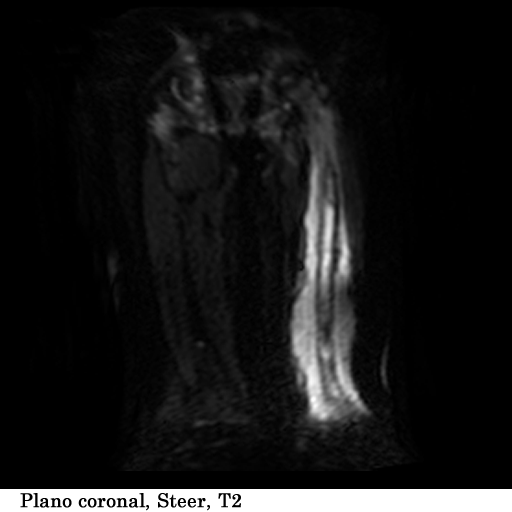

Paciente femenina, de 18 años de edad, con masa visible y palpable a nivel del tercio medio e inferior del fémur izquierdo, con un tiempo de evolución de 1 año, refiere dolor y limitación al movimiento.

TECNICA EMPLEADA

Se coloco al paciente en decúbito supino, utilizando una bobina fase array, haciendo adquisiciones en los planos axial, sagital y coronal, secuencias, spin echo, eco de gradiente e hibridas, potenciadas a T1, T2 y DP, secuencias Steer, y se obtuvieron imágenes con saturación de grasa.

HALLAZGOS IMAGENOLOGICOS

1. Edema de tejidos blandos que infiltra los músculos del muslo en su tercio medio y distal

2. Fractura patológica de tercio proximal de la diáfisis femoral izquierda

3. Engrosamiento del periostio del tercio medio y distal de la diáfisis femoral izquierda